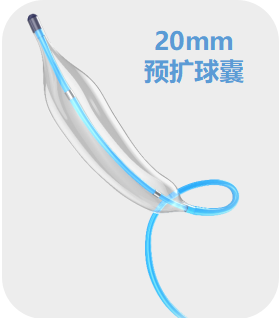

▶ 预扩张:20mm球囊。

20mm球囊预扩,可见腰征

20mm球囊后扩

▶ 预扩张:20mm球囊。

20mm球囊预扩,可见腰征

在冠脉保护下,20mm球囊后扩